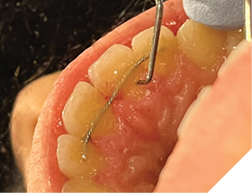

Fig. 1A

Fig. 1B

Fig. 1C

The majority of the orthodontic practices offer a period of “supervised retention” to their patients and communicates the customized retention recommendation with the patient’s general dentists. It is extremely important to work as a team to achieve long term clinical success in maintaining a functional bite and aesthetic smile. The general dentists continue to see their patients on a regular basis and have an opportunity to assess the orthodontic retainers and the bite after the supervised retention period is completed by the orthodontists. With great care, orthodontic retainers would serve for a long time (Fig. 1) without any major issues. However, in some cases, the failure to notice the clinical problems early on results in functional issues that would require a comprehensive orthodontic treatment to correct it (Fig. 2).